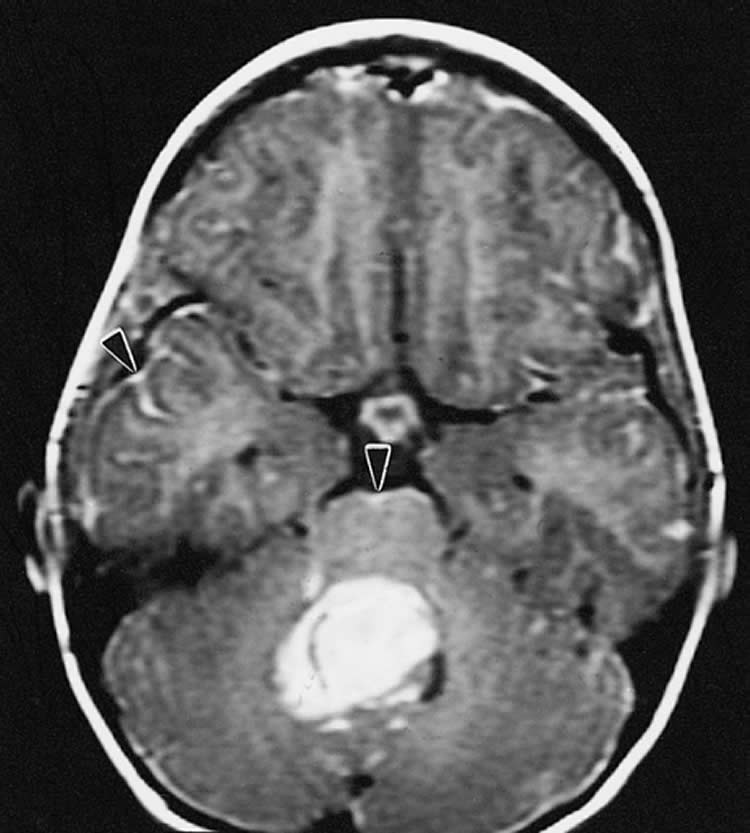

Image Source: The image is credited to The Armed Forces Institute of Pathology and is in the public domain